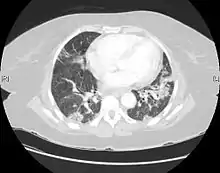

CT scan of a patient with UIP. There is interstitial thickening, architectural distortion, honeycombing and bronchiectasis.

Usual interstitial pneumonia seen on CT scan. Honeycomb fibrosis is seen at the bases of both lungs.

UIP may be diagnosed by a radiologist using computed tomography (CT) scan of the chest, or by a pathologist using tissue obtained by a lung biopsy.

Radiologically, the main feature required for a confident diagnosis of UIP is honeycomb change in the periphery and the lower portions (bases) of the lungs.[3]